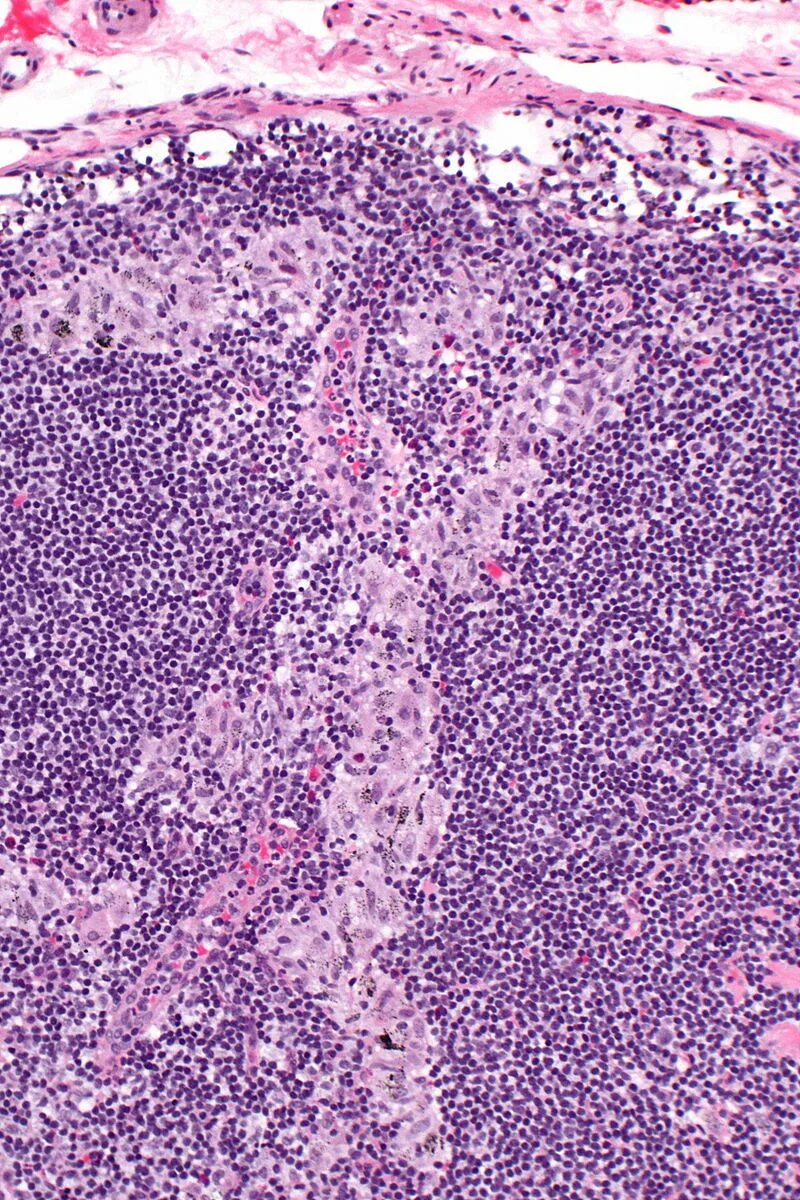

Синусовый гистиоцитоз лимфатического узла